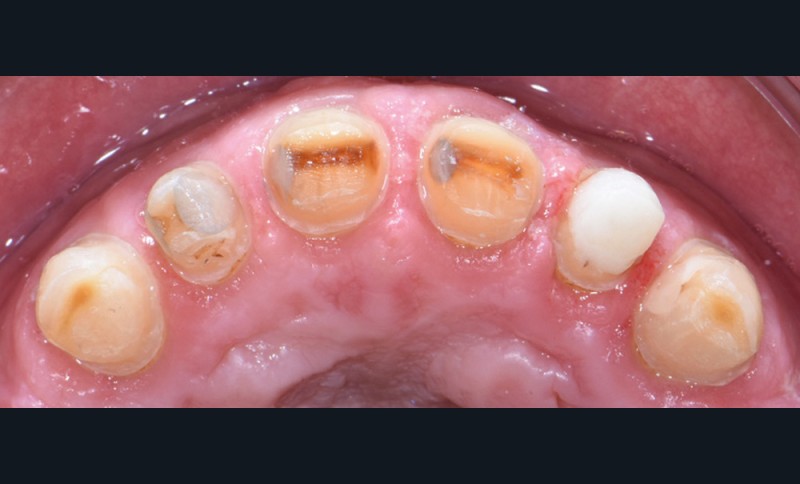

Au vu du contexte para-fonctionnel et de l’étendue de la perte tissulaire, des coiffes périphériques minimalement invasives ont été choisies afin de restaurer l’esthétique et la fonction. Actuellement, aucun consensus n’est fait sur le choix du matériau d’infrastructure à privilégier. Les matériaux hybrides usinables présentent des propriétés mécaniques, physiques et biologiques intéressantes en contexte d’usure sévère (e.g., module d’élasticité, résistance à la propagation de fêlures, facilité de réintervention). Une réhabilitation globale avec remontée de dimension verticale d’occlusion (DVO) par l’intermédiaire de coiffes composites renforcés en nano-céramiques est décrite.